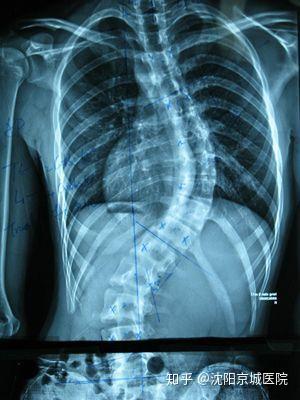

強(qiáng)直性脊柱炎的長期影響可能包括脊柱的彎曲、后凸或側(cè)凸,這可能會(huì)影響到患者的身高和體態(tài),由于脊柱活動(dòng)度的降低,患者可能會(huì)遭受行動(dòng)不便的困擾,在嚴(yán)重的情況下,強(qiáng)直性脊柱炎可能會(huì)導(dǎo)致肺、腸道等內(nèi)臟器官的功能障礙,由于炎癥的影響,患者可能會(huì)出現(xiàn)貧血、骨質(zhì)疏松等并發(fā)癥。

早期診斷和干預(yù)對(duì)于控制強(qiáng)直性脊柱炎的癥狀和防止病情惡化至關(guān)重要,醫(yī)生通常會(huì)根據(jù)患者的癥狀表現(xiàn)、體格檢查和可能的影像檢查結(jié)果(如X光、MRI)來診斷強(qiáng)直性脊柱炎,治療的目標(biāo)主要是控制炎癥、緩解疼痛、防止病情惡化和提高生活質(zhì)量,治療方法包括藥物治療(如非甾體抗炎藥、免疫抑制劑等)、物理治療(如物理療法、按摩等)和生活方式調(diào)整(如運(yùn)動(dòng)、保持良好的姿勢等)。